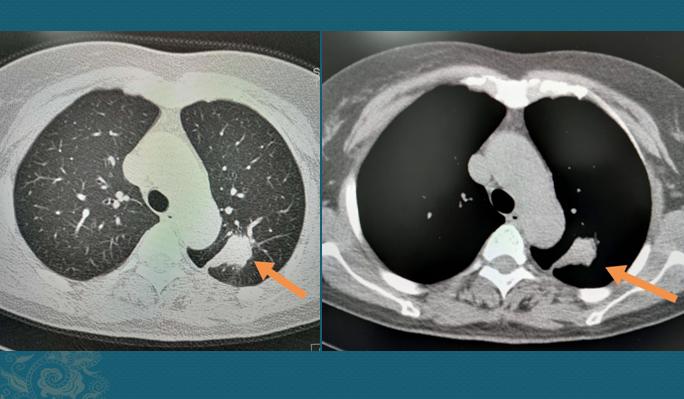

这是一个叫人费解的病例,中年女性,咳嗽、咳痰20多天,最近10天发现痰里有血,有时是血丝,有时是暗红色血块,心里很害怕,过来做了肺部CT:

左上肺长了个东西,形态不规则,与背侧胸膜有牵连,肺门侧小气管堵塞,高度怀疑肺癌。